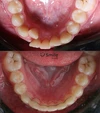

Zirkonyum uygulamalar

Porselen uygulamaları

Laminate veneer